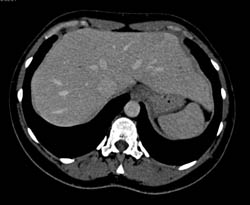

Focal Nodular Hyperplasia (FNH)